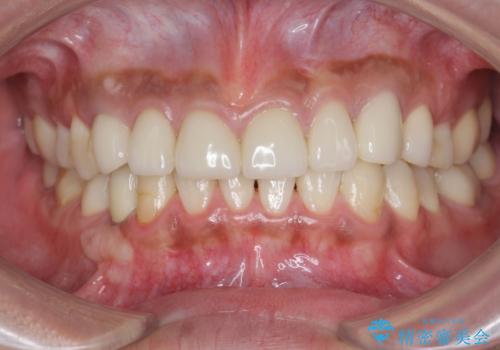

[メタルフリー] 虫歯・銀歯だらけの口腔内を全顎治療

![[メタルフリー] 虫歯・銀歯だらけの口腔内を全顎治療の症例 治療後](https://seimitsushinbi.jp/wp/wp-content/uploads/2025/03/530cf6cca6451bc106a9fb69dd58908a-500x350.jpg?v=1741918343)